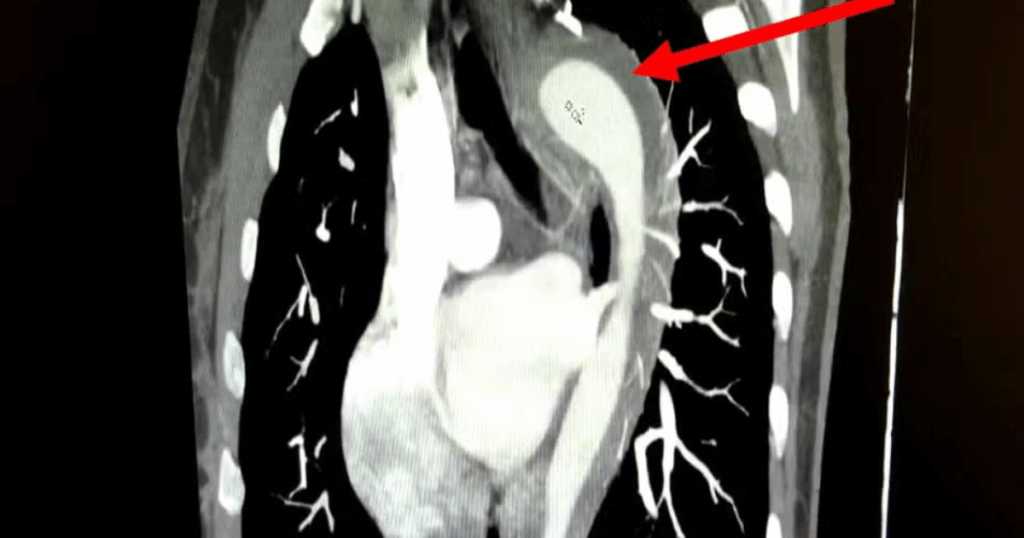

Exames revelaram um hematoma intramural na aorta — sangramento na parede da artéria, condição grave que pode levar a rupturas fatais se não tratada.